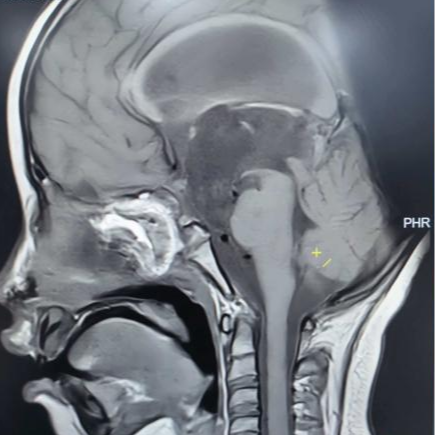

术后垂体MRI增强检查

手术中,团队借助高清4K神经内镜,凭借精湛的显微操作技术,细致分离肿瘤与周围神经、血管的粘连。历经3小时,肿瘤被完整切除,下丘脑、垂体柄、视神经等重要结构均得到完好保护。术后病理确诊为颅咽管瘤。

在医护团队的精心照护下,欢欢神经功能障碍明显改善,视力逐渐恢复,头痛症状完全消失,梗阻性脑积水得到有效缓解。之后顺利拔除脑室引流管,未出现脑脊液漏、感染等并发症,内分泌功能也通过药物获得精准调控。